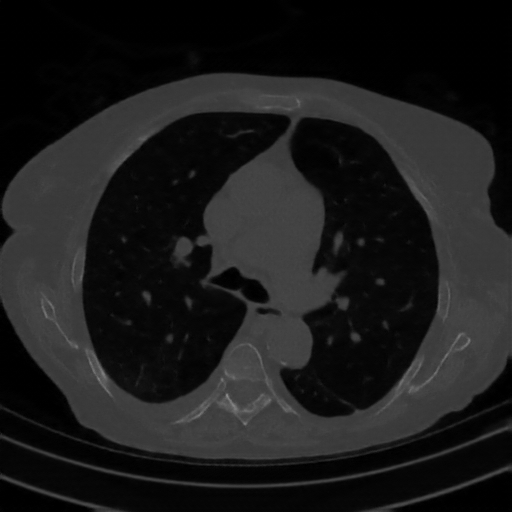

Reconstructed NATIVE CT scan (cycle consistency)

Full window (WL 1023.5, WW 4095 β†’ Low βˆ’1024, High +3071)

Lung window (WL -600, WW 1500 β†’ Low βˆ’1350, High +150)